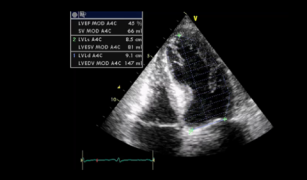

Assessing left ventricular global systolic function (LVF) with echo 25th Apr 2017 - Helen Rimington, PhD After watching this video, you will recognize normal, hyperkinetic and hypokinetic function of the left ventricle with ...